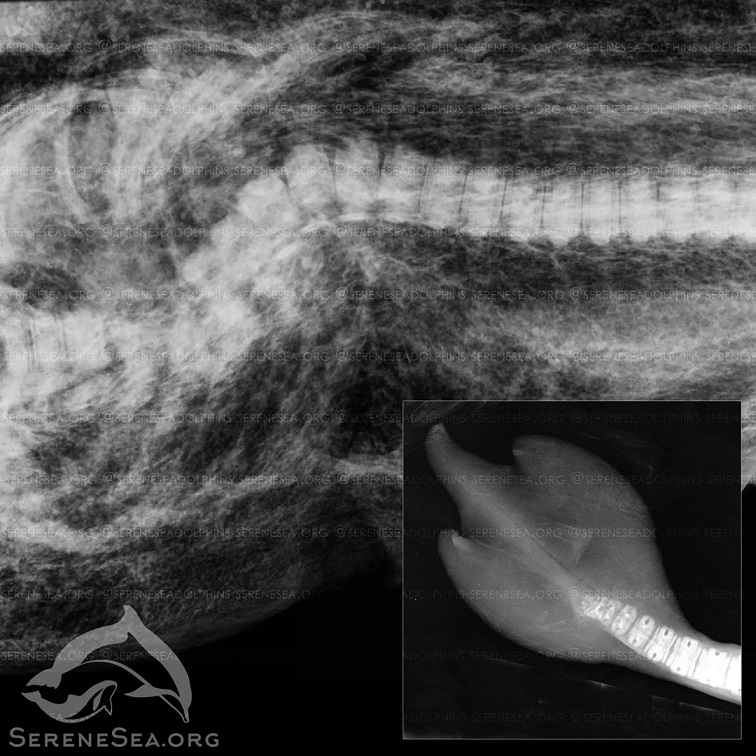

"На рентгенографии, помимо особенности строения лопастей, было выявлено сращение хвостовых позвонков. Особенности этих двух дельфинов имеют схожую природу, – не исключено, что они являются родственниками, а врожденная аномалия может быть результатом генной мутации", - отметили специалисты.

Найденный возле Алушты дельфин был новорожденным детенышем. С помощью рентгенографии у него выявили перелом позвоночника со смещением, который он, вероятно, получил вследствие удара взрослого агрессивно настроенного самца. Это и привело к его гибели.